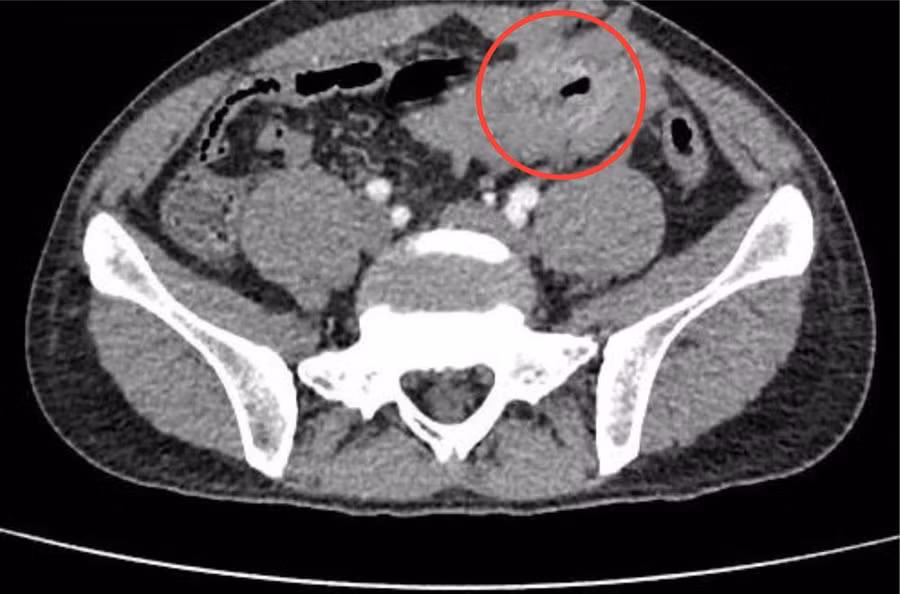

Qua thăm, khám sàng lọc kỹ lưỡng và thực hiện các cận lâm sàng cần thiết, các bác sĩ chuyên khoa ghi nhận người bệnh có một khối u GIST ruột non kích thước 3x5 cm đã có biến chứng thủng khối u gây viêm phúc mạc cấp ổ bụng.

Hình phẫu thuật nội soi u GIST ruột non. Nguồn: BV.